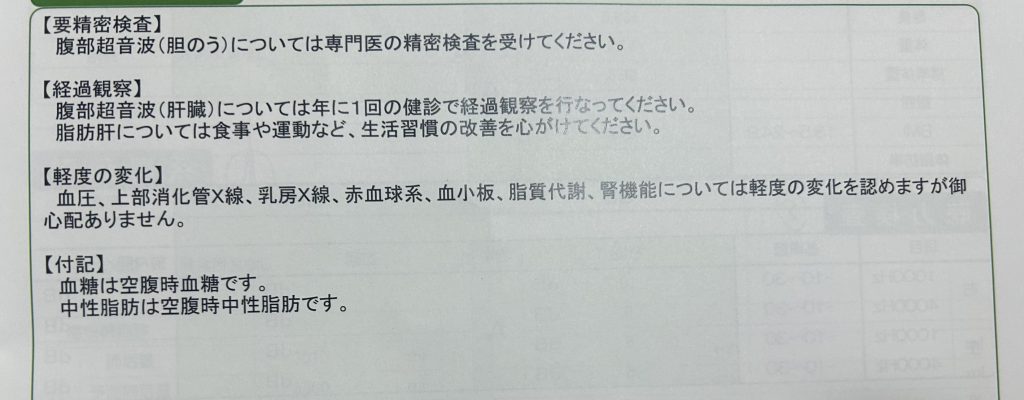

検査結果の到着

健康診断後3週間程度で検査結果とともに、案の定「要精密検査のお知らせ」が届きました。

腹部超音波の欄には「胆のう結石」というメモが記載されていました。大きさや数については言及されていませんでした。